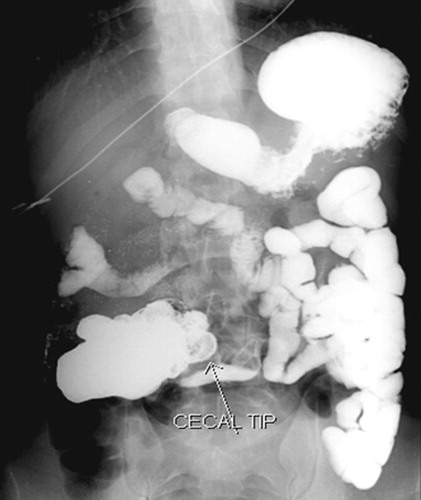

| Lower GI contrast | Performed when UGI is equivocal; demonstrates cecal position |

| DJJ right of midline | Abnormal; proximal small bowel loops to the right of midline |

Corkscrew sign may only be visible on one view. Always assess the duodenum on both frontal and lateral projections before concluding the study is normal. In partial volvulus, contrast may pass with a minimal twist — subtle beaking or rightward DJJ position may be the only clue.